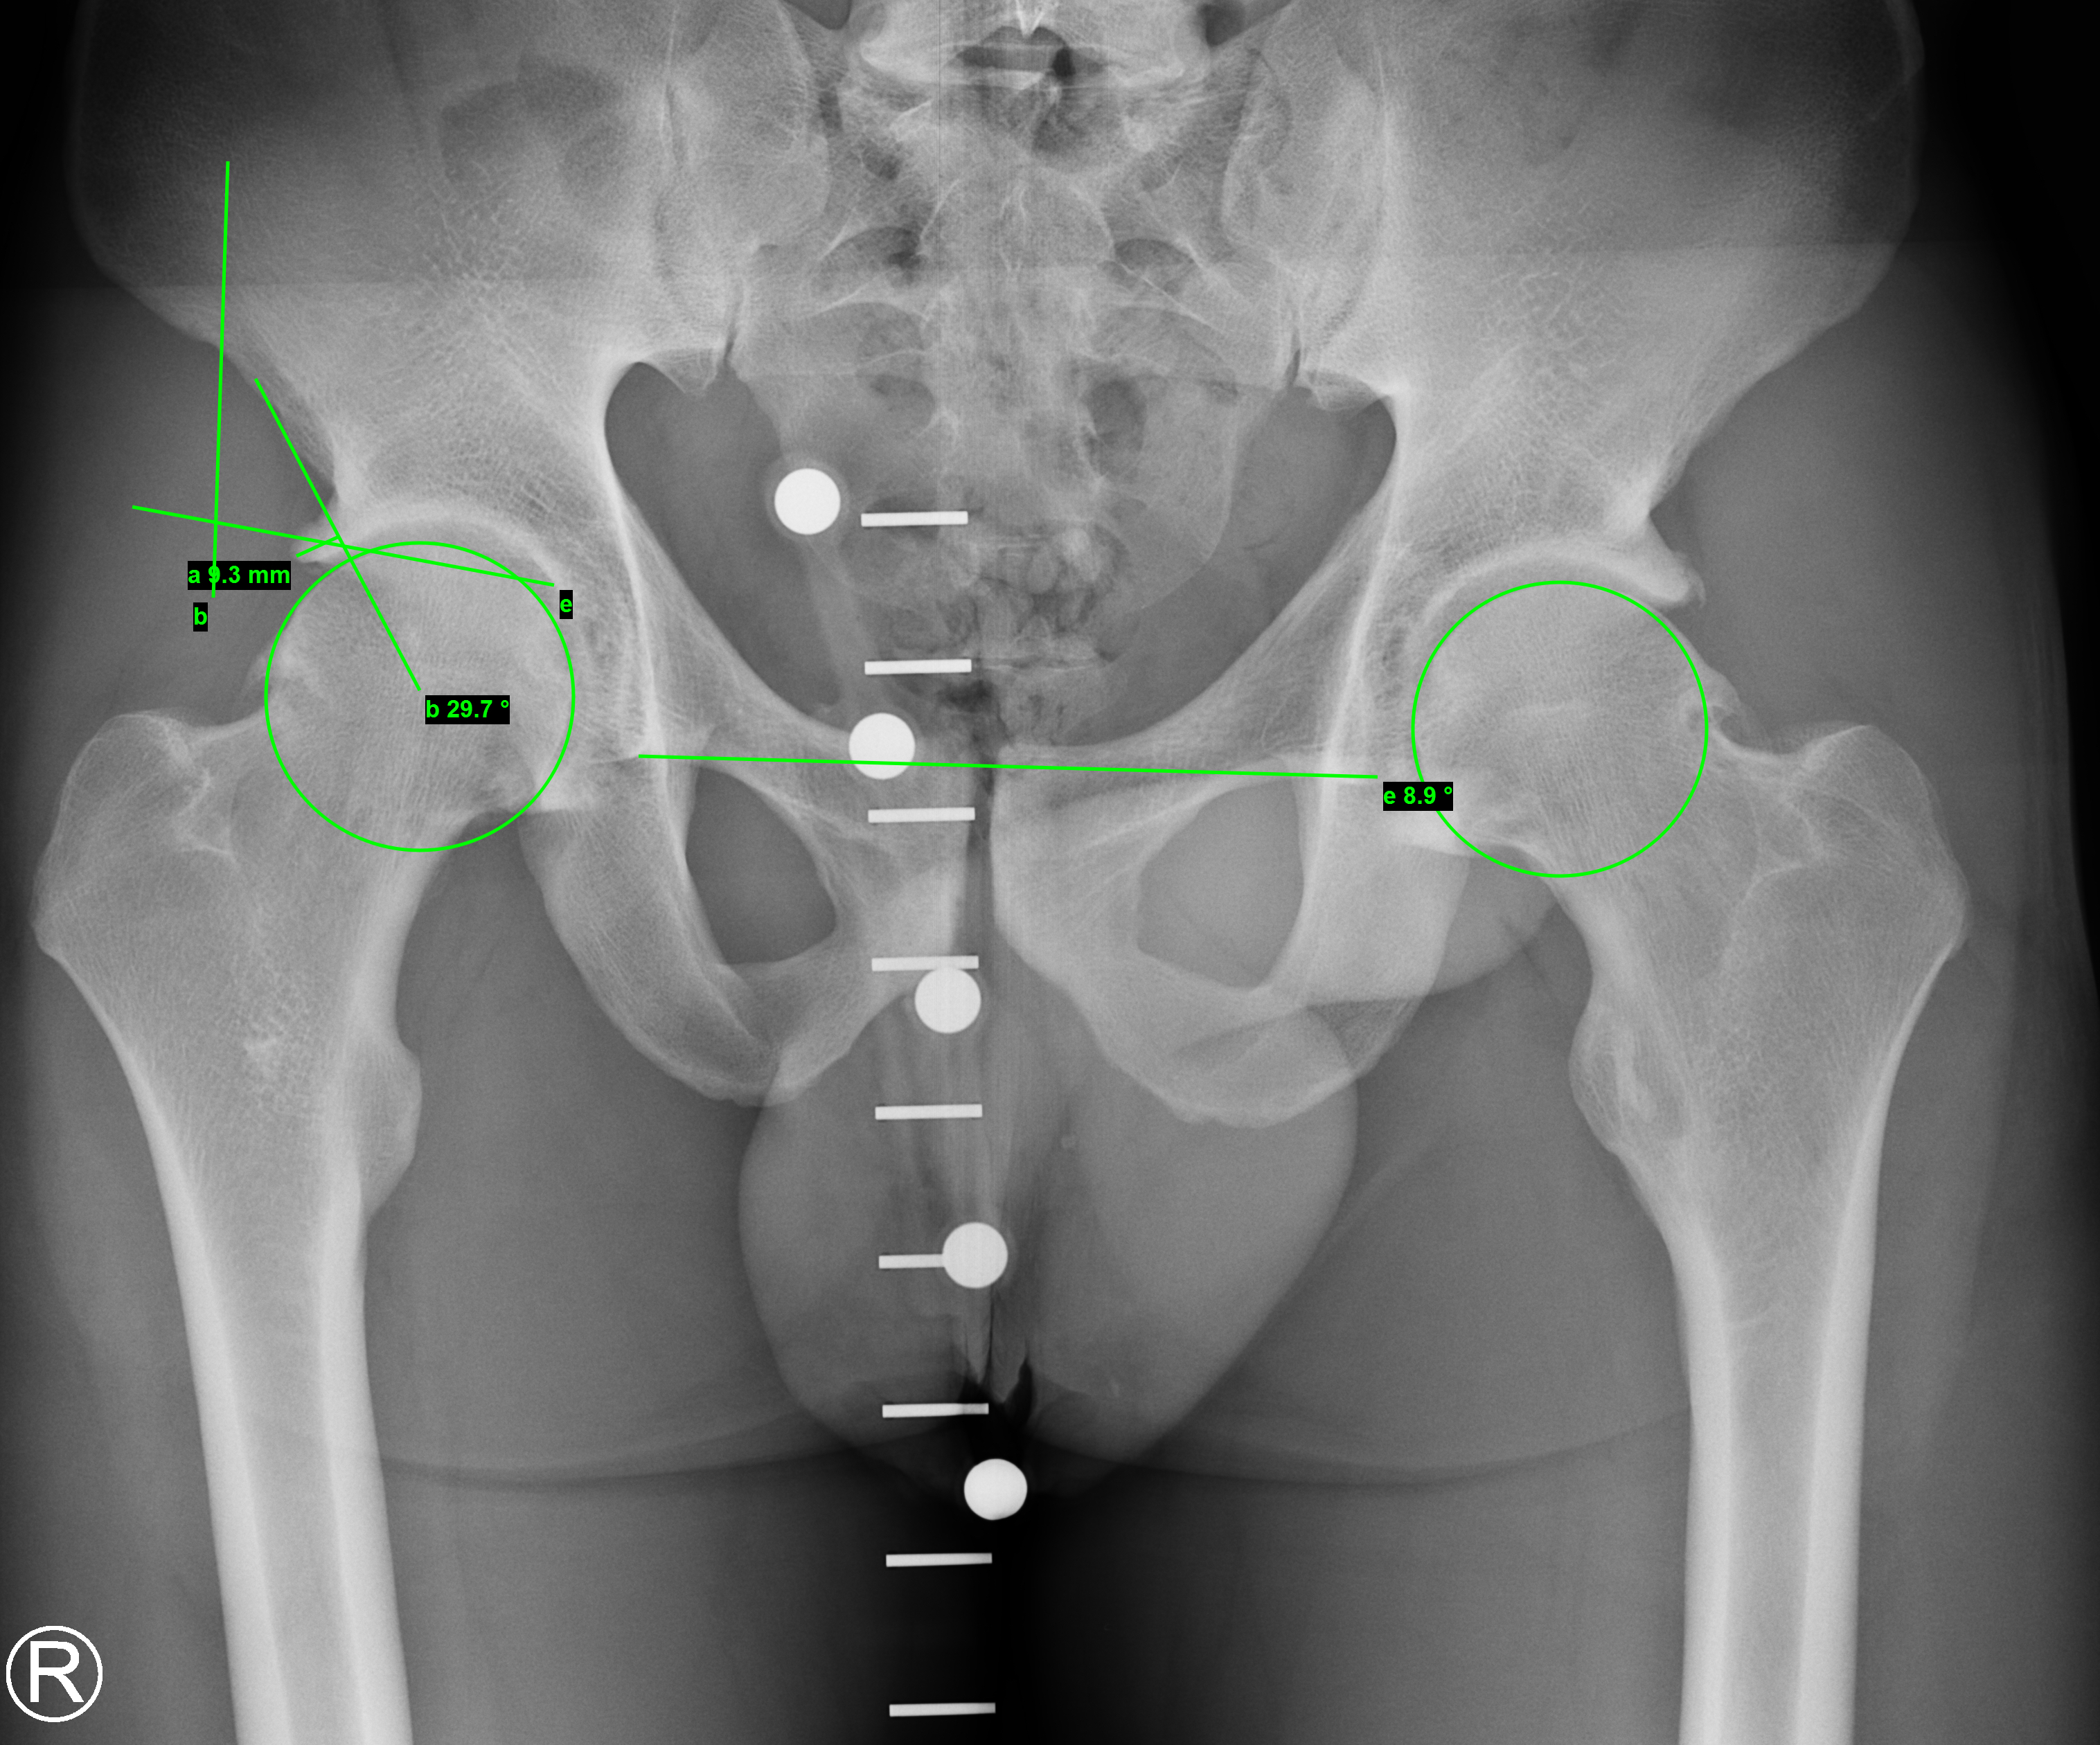

- Konventionelles Röntgen von Beckenübersicht und Dunn-View: Hier zeigt sich eine vermehrte Überdachung des Hüftkopfes durch das Becken. Anhand von Winkeln (CE- und AC-Winkel) wird das Ausmaß der Überdachung quantitativ bestimmt und bei vermehrter Überdachung besteht der Nachweis eines Pinzer-Impingement (sog. Kneifzangenphänomen). Der rot markierte Knochen stellt den überschüssigen Knochen dar, der zu dem Pinzer-FAI führt und im Rahmen einer Operation abgetragen werden kann.

- Femoroazetabuläres Impingement Typ CAM- und Pinzer mit Knorpelschaden am seitlichen Pfannenrand